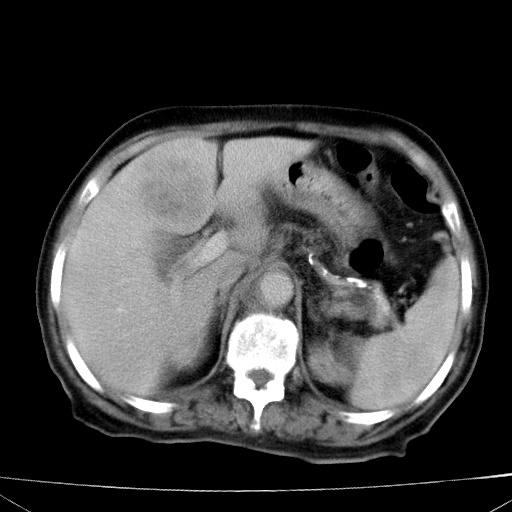

网站人气太旺!昨天的帖子就沉到海底,只好再发贴!ct18338:女 78岁,肝胆病变,已增强,再会诊!原帖链接:http://www.radida.com/bbs/forum.php?mod=viewthread&tid=50032

1)考虑胆囊癌侵犯肝脏并肝门区、腹膜后及右侧膈角后淋巴结转移。2)肝左叶近肝顶部囊肿。3)肝左叶肝内胆管结石。4)左肾近下极囊肿。

1、胆囊癌侵犯肝脏并腹腔及腹膜后淋巴结转移。

2、肝左叶外侧段囊肿。